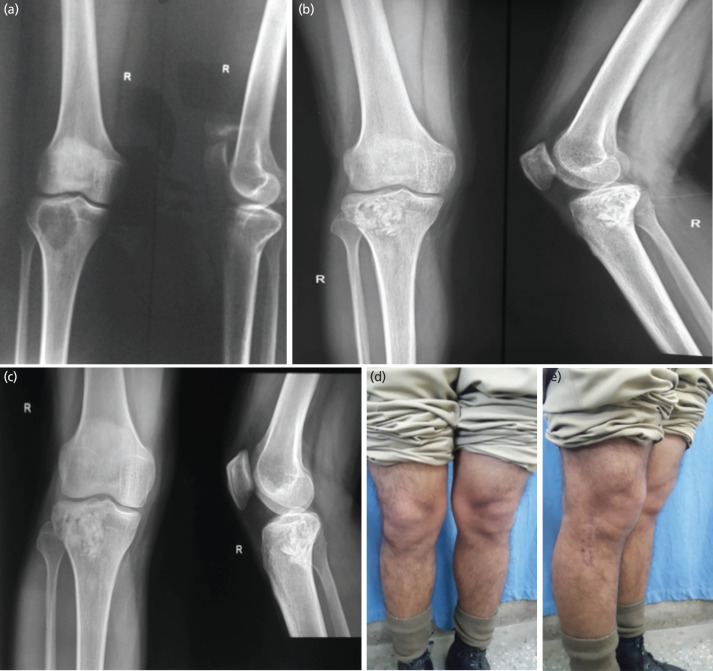

Material and methods: All patients with biopsy-proven GCT, involving either the distal femur or proximal tibia, and treated with either curettage with bone grafting (CBG), curettage with bone cementation (CBC), or curettage combined with grafting and cementation (the Sandwich technique) were included. They were further classified according to Campanacci grading. Patients were followed for a minimum of two years, and all complications were recorded.

Results: The three groups showed a statistically significant difference in terms of persistent pain after surgery (p=0.03), development of long-term arthritis (p=0.01), as well as overall complications (p=0.005). There was no significant difference in terms of the overall recurrence rate between each group (p>0.05). For Campanacci Grade II lesions, there was a statistically significant difference in terms of local recurrence (p=0.01), with lower recurrence rates observed after cementation procedures.

Conclusion: The study indicates that the Sandwich technique was associated with a lower rate of complications compared to CBG or CBC. Patients in the CBG group reported persistent pain, while those in the CBC group exhibited early arthritic changes within five years of the index surgery. Although there was no overall difference in recurrence rates, cementation procedures had a significantly lower rate of recurrence in Campanacci Grade II lesions.